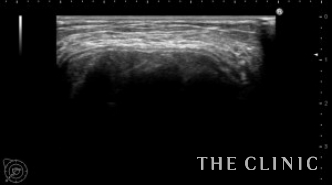

エコー所見です。石灰化の強いしこりです。